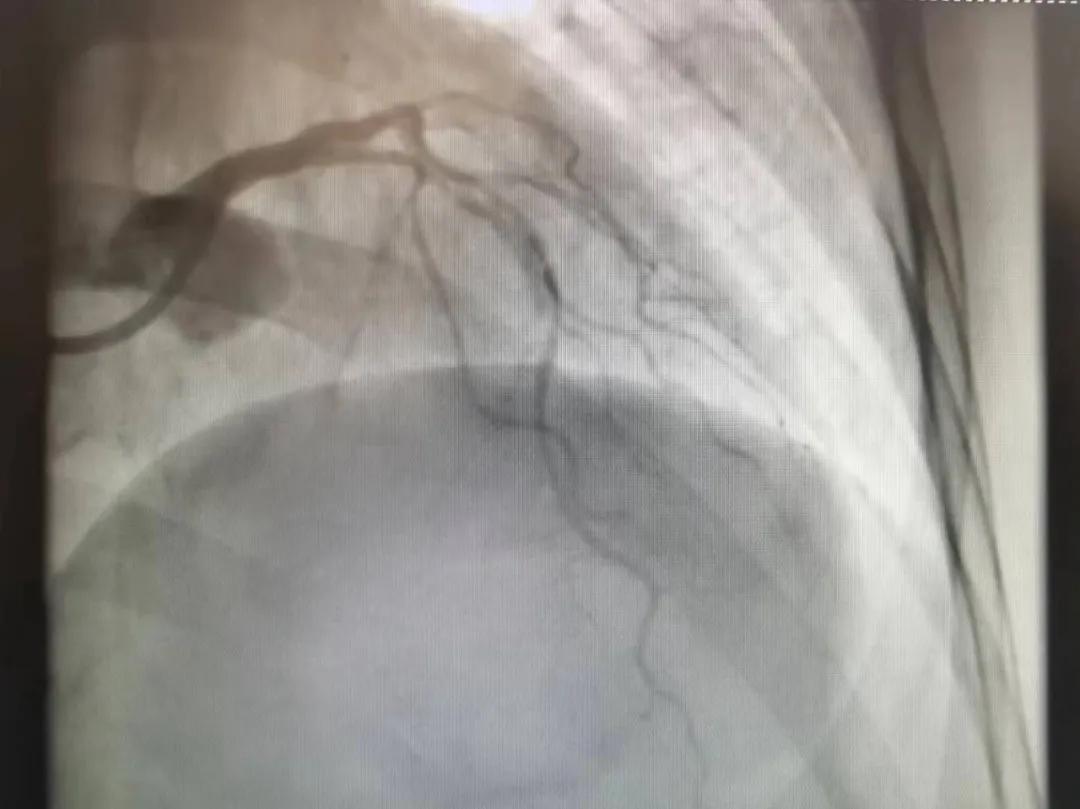

王瑾院長和李慧新主任帶領(lǐng)介入團隊充分評估,決定行前降支冠狀動脈鈣化病變旋磨術(shù),術(shù)中應(yīng)用1.5mm旋磨頭,以15萬-17萬轉(zhuǎn)/分速度共對病變旋磨3次,累計旋磨時間60秒,后復(fù)查造影示鈣化明顯減輕,為后續(xù)操作創(chuàng)造了良好條件,隨后應(yīng)用預(yù)擴張球囊、切割球囊再次處理病變,并順利植入支架1枚,復(fù)查造影顯示支架膨脹及貼壁良好,無夾層、血腫、慢血流等情況,手術(shù)順利完成。患者術(shù)后無不適,胸悶、胸痛癥狀明顯緩解,順利出院。

術(shù)后